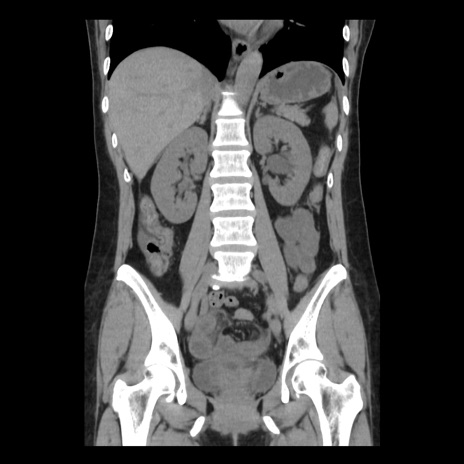

症例10(冠状断像)

【症例】 50歳代女性

【主訴】 腹痛

【現病歴】前日生レバーを食べた。今朝に排便あり。 昼前に突然発症の腹痛を生じ、当院救急外来を受診した。

【既往歴】 子宮筋腫にてで子宮全摘後

【身体所見】 意識清明、腹部:平坦、軟、下腹部やや左を中心に圧痛・反跳痛あり、筋性防御あり

【データ】WBC 7800、CRP 0.07